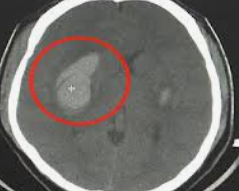

뇌출혈을 정확히 진단하기 위해서는 뇌 CT나 MRI 검사를 진행합니다. CT 검사는 빠르게 출혈의 위치와 크기를 확인할 수 있어 응급 상황에서 중요한 역할을 합니다. 또한 혈액검사를 통해 혈액 응고 상태를 확인하고, 필요한 경우 뇌혈관조영술을 통해 출혈의 원인인 혈관 문제를 파악할 수 있습니다.